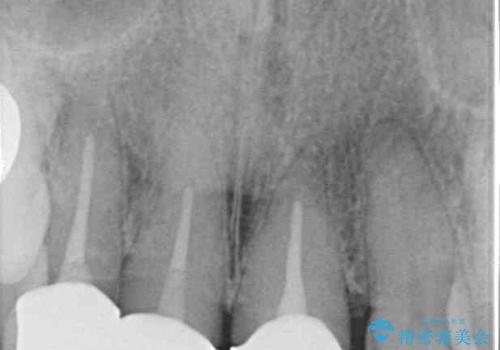

- 20年以上前に装着した前歯のメタルセラミックが不自然であることを気にして来院された患者様です。

歯肉の位置が変わり、変色した歯根が露出しているため、金属の土台をファイバーコアに交換した上で、オールセラミッククラウンにて補綴することとしました。